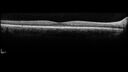

Paclitaxel induced cystoid macular edema - reversed when chemo stopped25 views74 year old retired physician About 2-3 weeks ago there was gradual vision loss in the right eye. The patient was seen by an ophthalmologist who saw macular swelling and injected vabysmo. He has been on chemotherapy (Carbiplatin and Carboxytaxol for 2 cancers - advanced prostrate diagnosed 2019 - has had brain surgery AND squamous lung cancers treated with radiation)

Medical Hx: Prostate cancer (Onset: 2018). Pulmonary and bone cancer metastatic. Brain cancer metastasized from prostate cancer.

Surgical Hx: Right frontal & Frontoparietal Craniotomy (Onset: 2024). Appendectomy. Hemorrhoidectomy. Herniorrhaphy. Prostate. Systemic Meds: Chemotherapy. Radiation. Eligard Every 3 Months 22.5 MG per 0.375 ML Prefilled Syringe. MIRALAX prn. Tums Freshers 500 MG Chewable Tablet. Vitamin D. XGEVA.

VA OD: Dcc20/125+1

VA OS: Dcc20/125-2

TP: OD:12 OS:15Aug 17, 2025